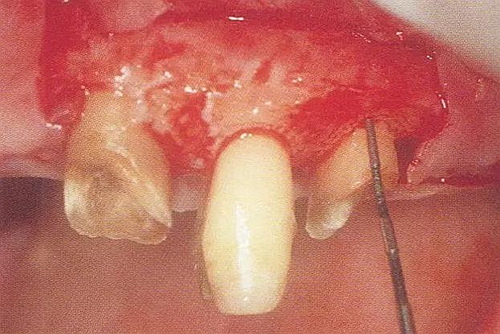

▼圖10-5(左)  利用骨膜分離器進行全厚瓣翻瓣。根面處留存一層薄薄的包含牙周袋內(nèi)緣上皮的組織(頸領(lǐng))。

▼圖10-6(右)  除去牙冠周圍組織的狀態(tài)。將肉芽組織完全去除后,出血變少牙槽骨和牙根的移行部變得明了,徹底清理變得更容易。